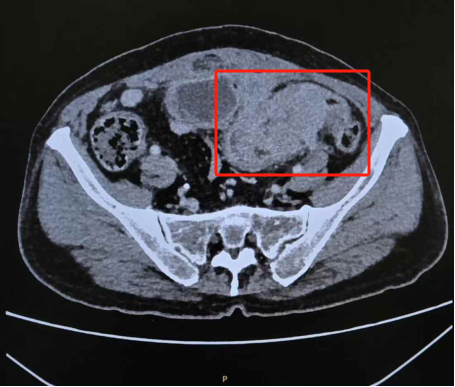

宋禾副教授接诊后为其完善相关检查,增强CT结果提示患者乙状结肠占位性病变侵犯盆壁、膀胱,电子结肠镜病理诊断明确为腺癌。由于肿瘤病期较晚,患者已出现不全肠梗阻以及离子紊乱,同时伴有结肠膀胱瘘,出现尿便混杂,已经引发严重泌尿系统感染,若不及时干预,短时间内即可能出现器官功能衰竭。但棘手的是,鉴于复杂的病变特点和侵袭程度,单科室手术既无法完整切除肿瘤,又难以保障膀胱功能。

CT显示乙状结肠恶性肿瘤侵犯盆壁、膀胱